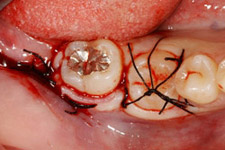

移植直後

移植直後。歯根がまだ完成していない歯では、根の先が開いていることに気づきます。